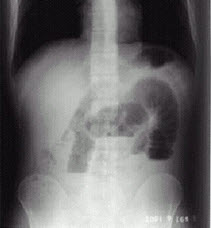

病史:男性,46岁,腹胀、腹痛3天,停止排便。诊断:()

A、肠结核

B、正常腹平片

C、消化道穿孔

D、肠梗阻

E、以上均否

D